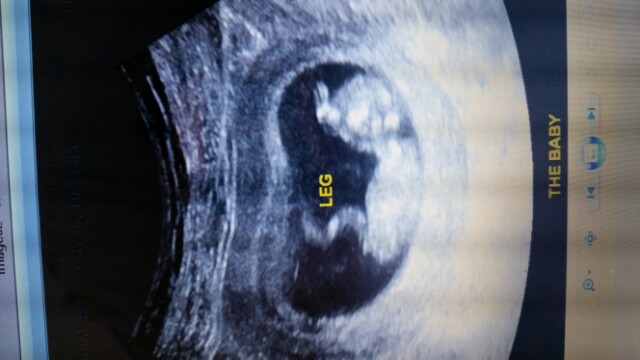

11w3d Ultrasound

Nub Theory?

interested to know what your guesses are! Heart rate was 179.